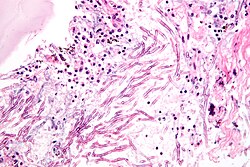

Micrograph showing a mycosis (aspergillosis). The Aspergillus (which is spaghetti-like) is seen in the center and surrounded by inflammatory cells and necrotic debris. H&E stain.